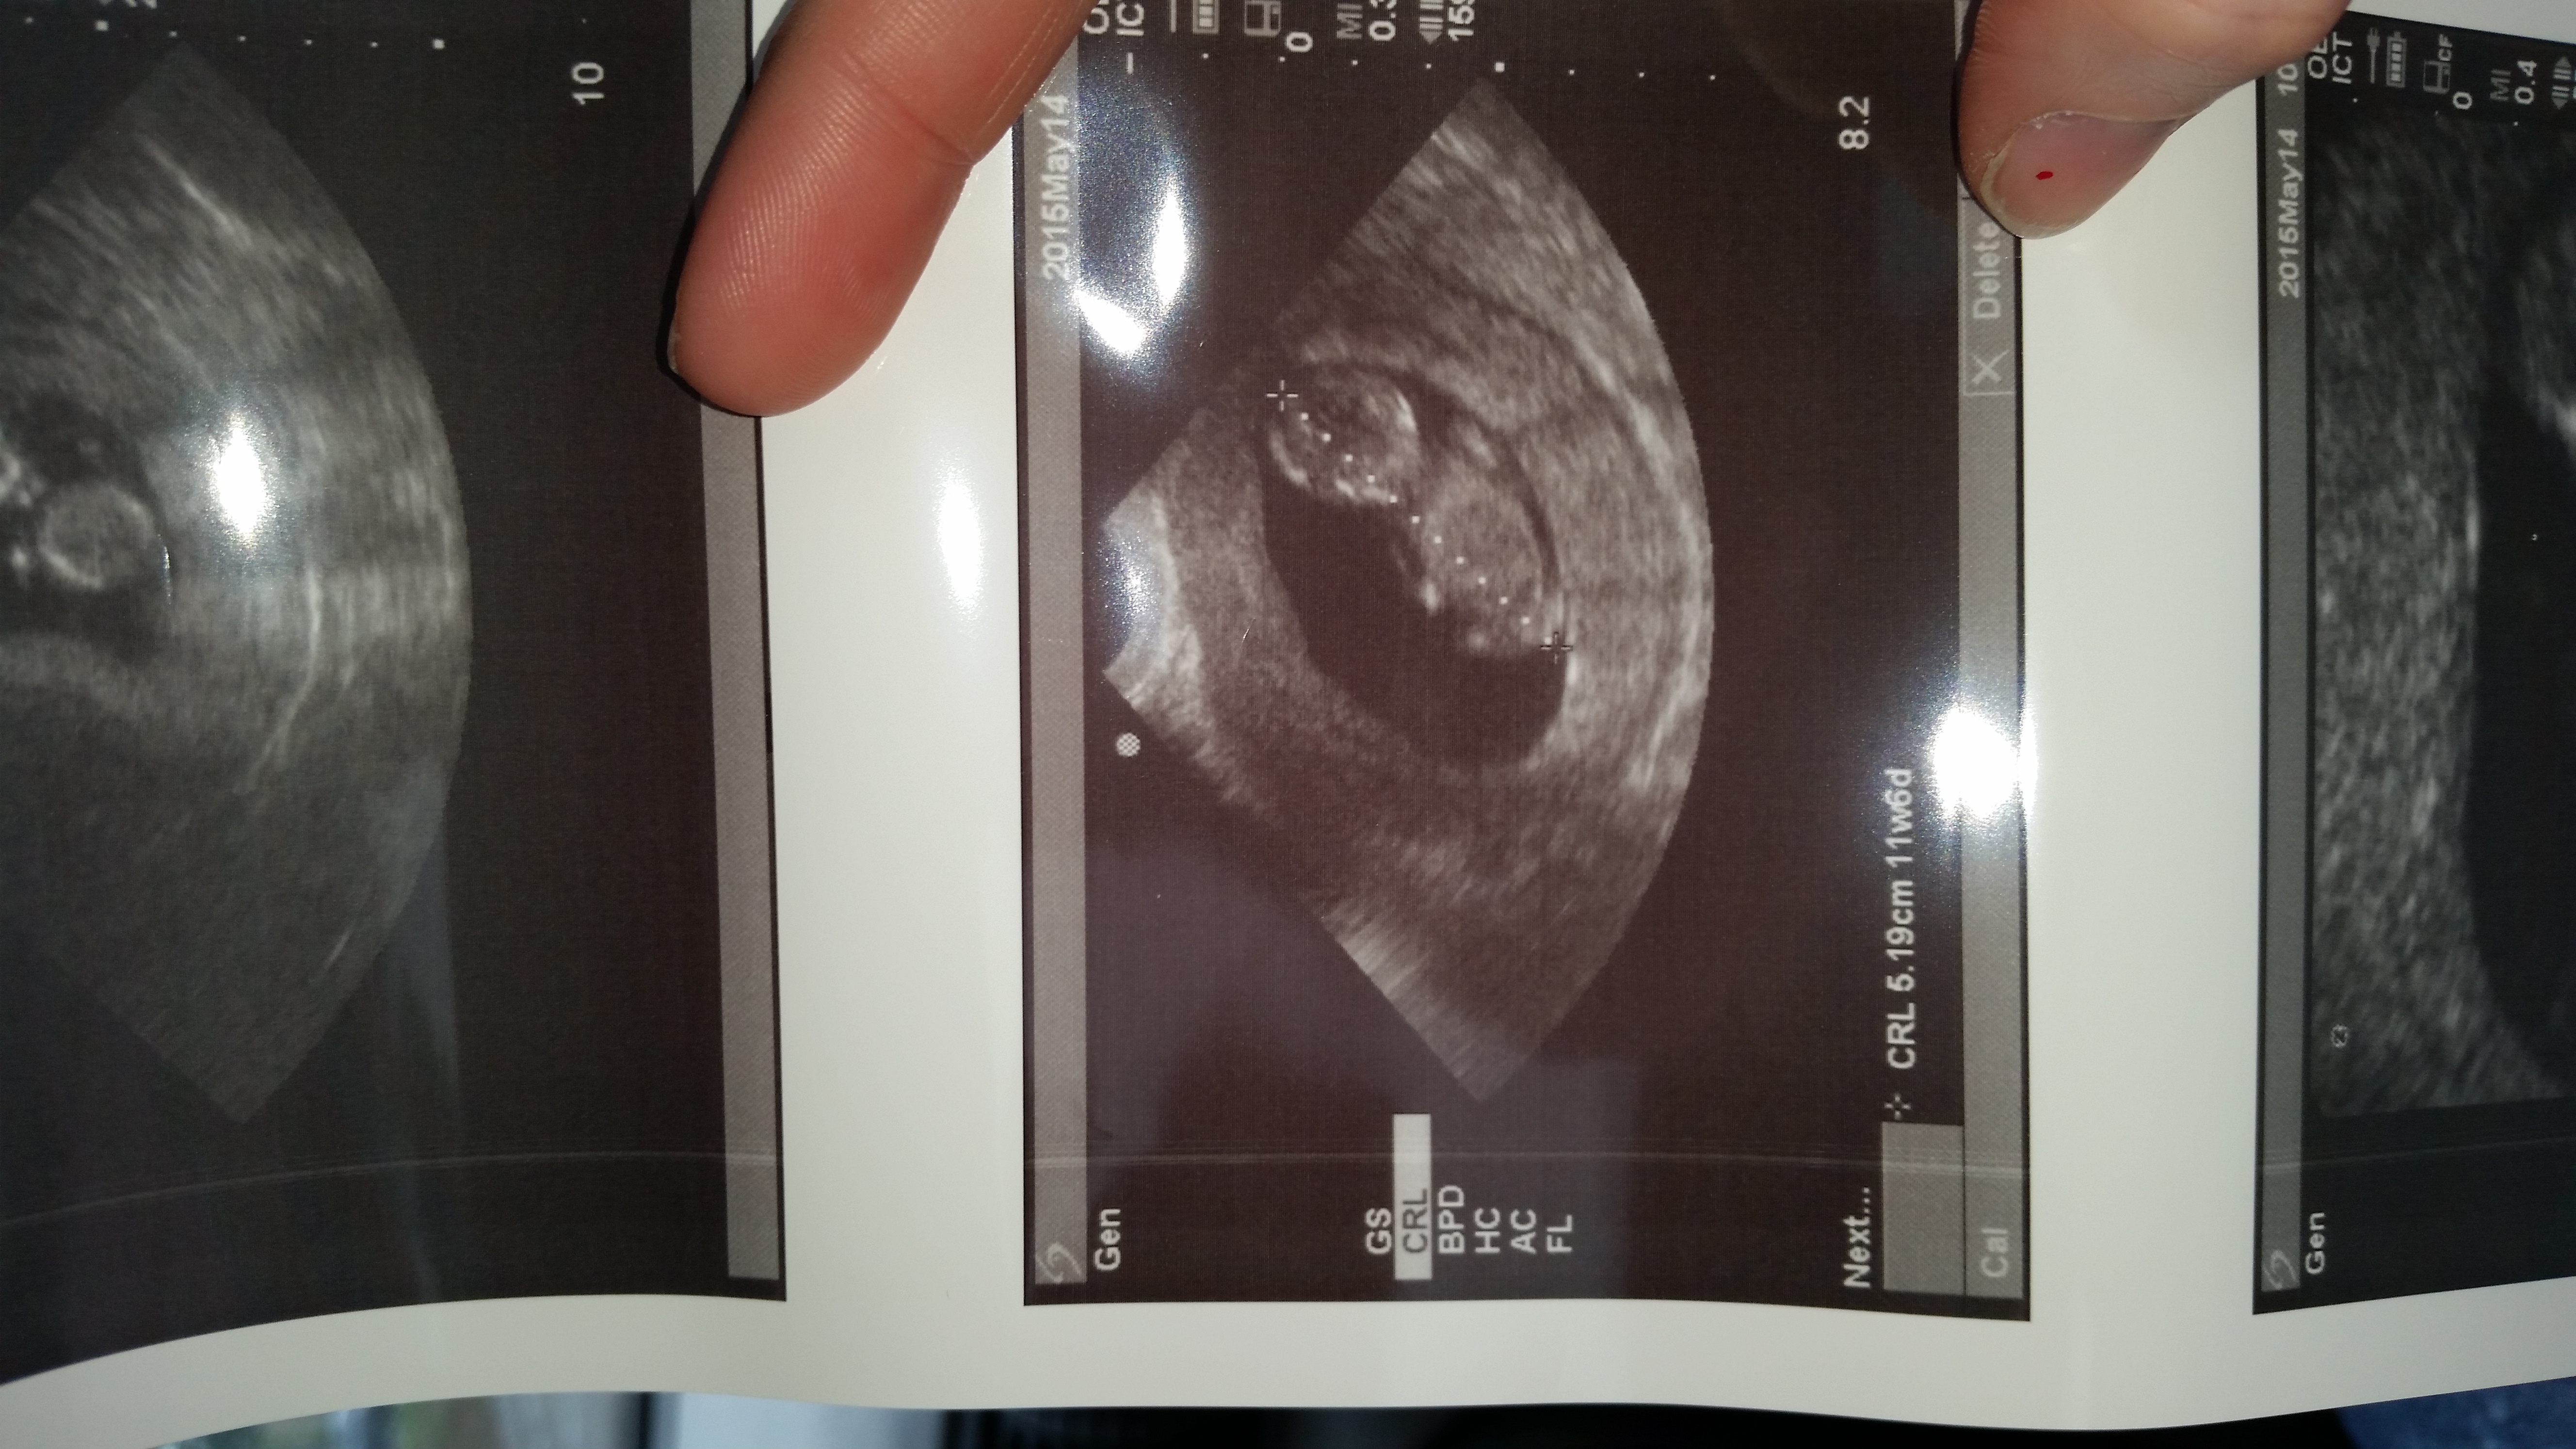

I was 9 weeks, obgyn asked for an ultrasound since I only had one at 5 weeks and it was a empty sac. Such a relief since I read to much into things. Heartbeat was 164. It was kicking and flipping on its head. I teared up since my last pregnancy ended as an ectopic. * that is a foot not a peepee ☺️